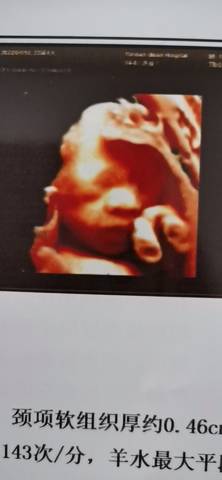

有会看男宝女宝的吗?今天四维一次过了,做了半个多小时一直不给看脸,后面终于看到了

journal_insert_pic_1685638406journal_insert_pic_1685638411